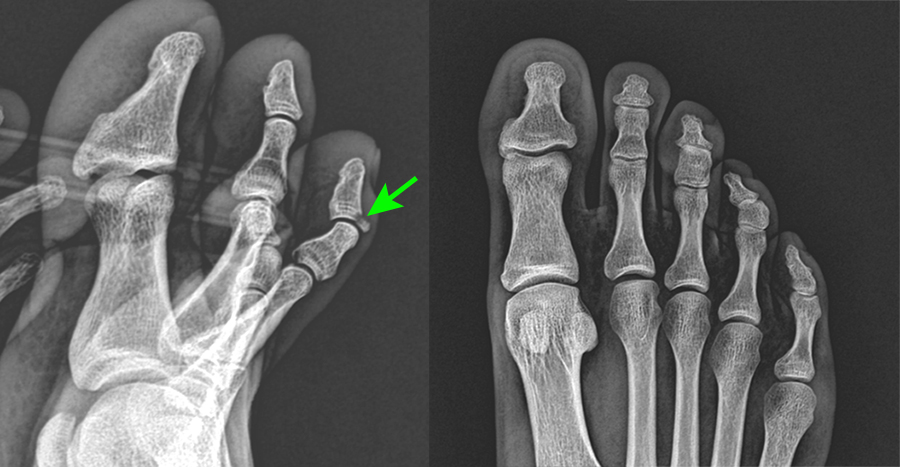

발가락 골절 후, 의료 서비스 제공자와 상담이 필수입니다. 의사는 X-레이 및 기타 진단 검사를 통해 골절 정도를 평가하고 적절한 치료 방법을 제시할 것입니다. 부상된 발가락은 부목, 깁스 또는 테이핑을 통해 안정화될 수 있습니다.